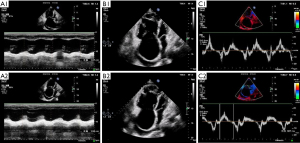

The results from blind evaluation of echocardiography parameters were highly consistent with the results obtained for RHC parameters (Figure 3). All examinations were performed within 24 h. PASP at baseline was 62.90±27.70 mmHg as determined by echocardiography, as opposed to 60.97±21.13 mmHg as determined by RHC. RHC and echocardiography results were significantly correlated (r=0.807; P<0.0001). Echocardiography function parameters, echocardiography structural parameters and echocardiography PASP of the 30 patients before vs. after BPA are presented in Table 3. Notably, some echocardiography function parameters were significantly improved after BPA (Figure 2). In addition, echocardiography structural parameters were significantly improved after BPA. Right atrium parameters including RAD (54.62±9.86 vs. 51.61±9.97, P<0.001), RAEDA (19.31±7.43 vs. 17.61±6.52, P=0.002), RAESA (13.90±7.45 vs. 12.66±6.88, P<0.001) were significantly less after BPA relative to the values before BPA. In addition, right ventricular parameters including RVEDA (26.72±8.99 vs. 24.82±8.52, P=0.022), RVESA (18.19±8.35 vs. 16.51±7.93, P=0.013) decreased after BPA. Moreover, echocardiography PASP after BPA was significantly lower compared with that before BPA (62.90±27.70 vs. 57.02±24.99, P=0.047). However, the results showed no significant changes in S’, TAPSE, RIMP, RVFAC, and LVSV after BPA, however, the mean values of these parameters were slightly improved (P>0.05; Table 3). A representative echocardiography images of one CTEPH patient before and after BPA treatment is presented in Figure 4.